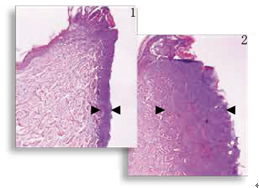

圖1,2

減輕熱損傷 組織學顯示,對比標準的電切尖端切口(圖2 ),表觀切口(圖1)明顯熱損傷減少